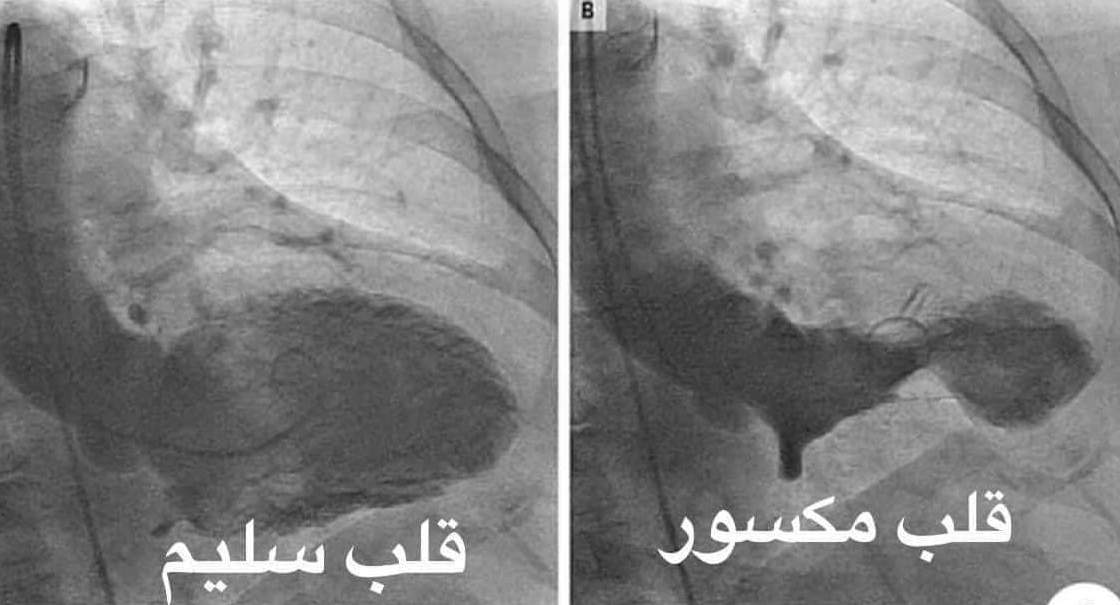

وقال جمال شعبان إن: "القلب المكسور ضعيف ومنكمش، والقلب السليم محتفظ بقوامه في شكله ووظيفته، الزعل والصدمات العاطفية، والفشل في الحب، وفقدان الأحبة بيكسر القلب، وممكن ينتهي بموت مفاجئ".

وعن أعراض انكسار القلب وجلطة الشريان التاجي قال الدكتور جمال شعبان: "أعراض جلطة الشريان التاجي.. وجع وذبحه، ورسم القلب ممكن يتشابه مع الجلطة، لكن قسطرة الشرايين التاجية بتطلع سليمة، العلماء سموا الحالة دي متلازم القلوب المنكسرة، هي منكسرة عاطفيًا وعضويًا. Broken heart syndrome"